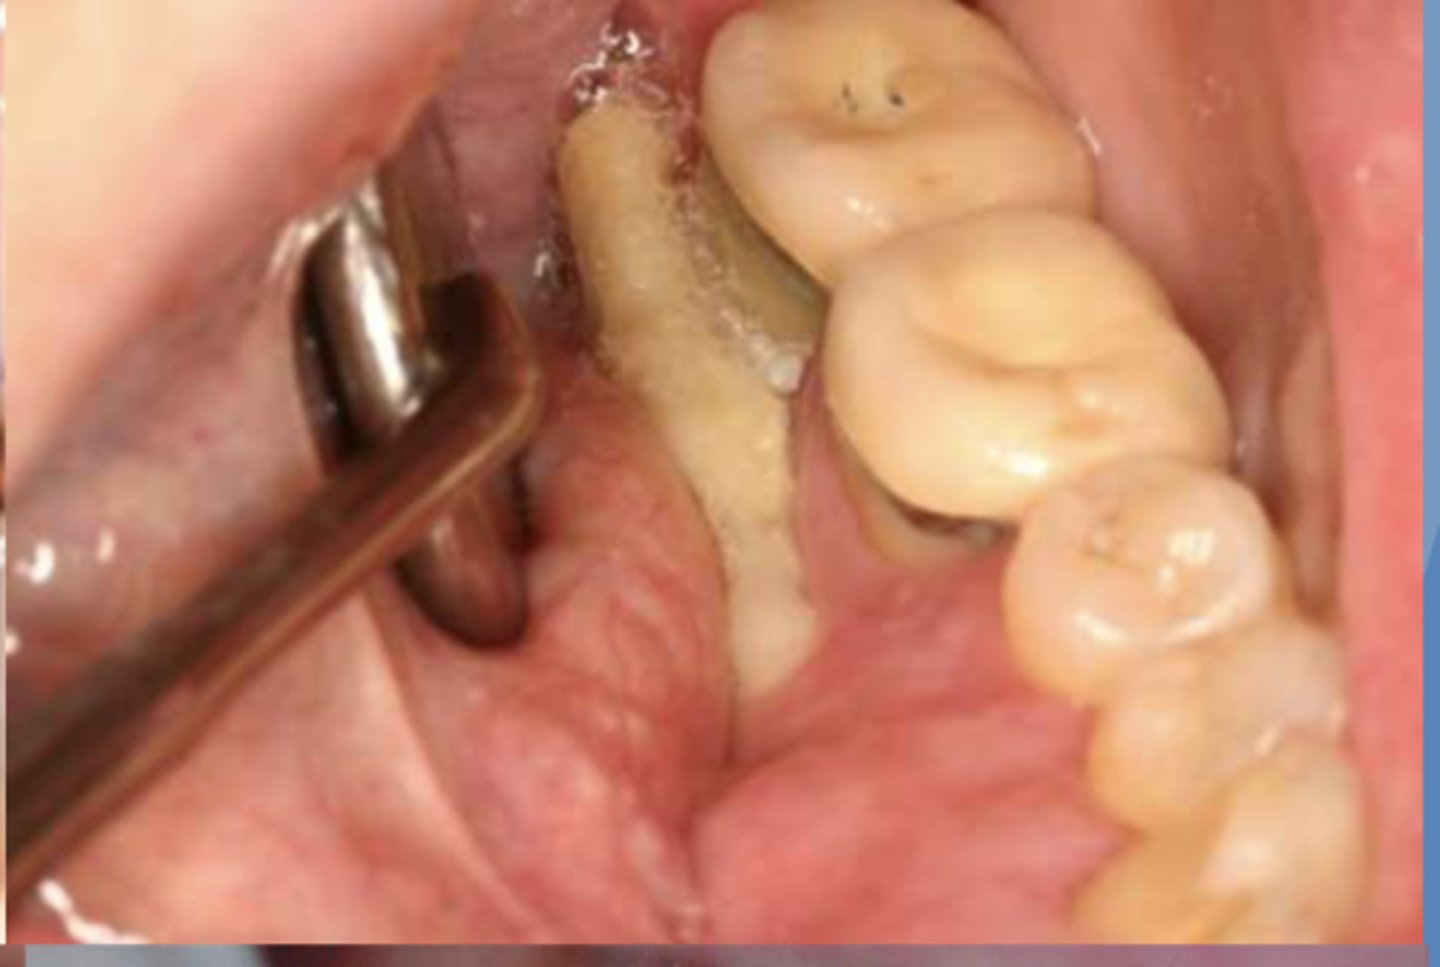

Upon clinical examination, you find a lesion that appears to be necrotic bone showing through the lingual attached gingiva of #31. What do you suspect? Is there anything you should look for in the patient history?

osteonecrosis/osteoradionecrosis/ MRONJ

*should see if patient is currently taking a bisphosphonate, undergoing head/neck radiation therapy, or on any other anti-resorptive or anti-angiogenic therapy

what do you suspect?